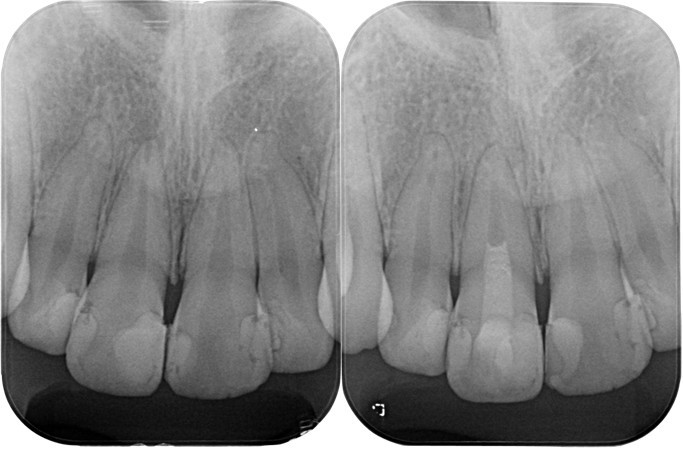

(図26)術後レントゲン像

左上1番以外は天然歯は全て有髄歯の状態で保存できている